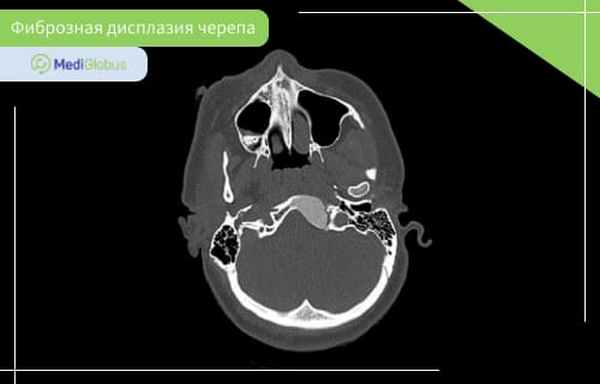

Фиброзная дисплазия костей черепа

Фиброзная дисплазия костей черепа встречается в 10-25% монооссальной формы болезни, и 50% – полиоссальной.

Чаще всего этот вид фиброзной дисплазии поражает переднюю часть черепа: лобную, клиновидную, решетчатую кость, верхнюю или нижнюю челюсть. Фиброзная дисплазия основания черепа встречается очень редко.

Симптомы фиброзной дисплазии черепа зависит от расположения образования. Болезнь может проявиться через заложенность носа, кривые зубы, асимметрию лица, выступающий лоб, выпученные или неправильно расположенные глаза. В некоторых случаях может быть деформация черепа. Степень поражения отличается от пациента к пациенту.

Фиброзная дисплазия костей черепа обычно не несет вред мозгу, нервам и кровеносным сосудам.

Диагностика фиброзной дисплазии костей черепа включает КТ, МРТ и рентген. Кроме этого, пациенту может понадобиться консультация невролога, челюстно-лицевого хирурга и стоматолога.

Хирургическое лечение фиброзной дисплазии черепа проводится в случае, если есть угроза нарушений зрения/дыхания или значительных внешних дефектов. Из-за сложности хирургии зоны лица полное удаление опухоли может быть невозможным.